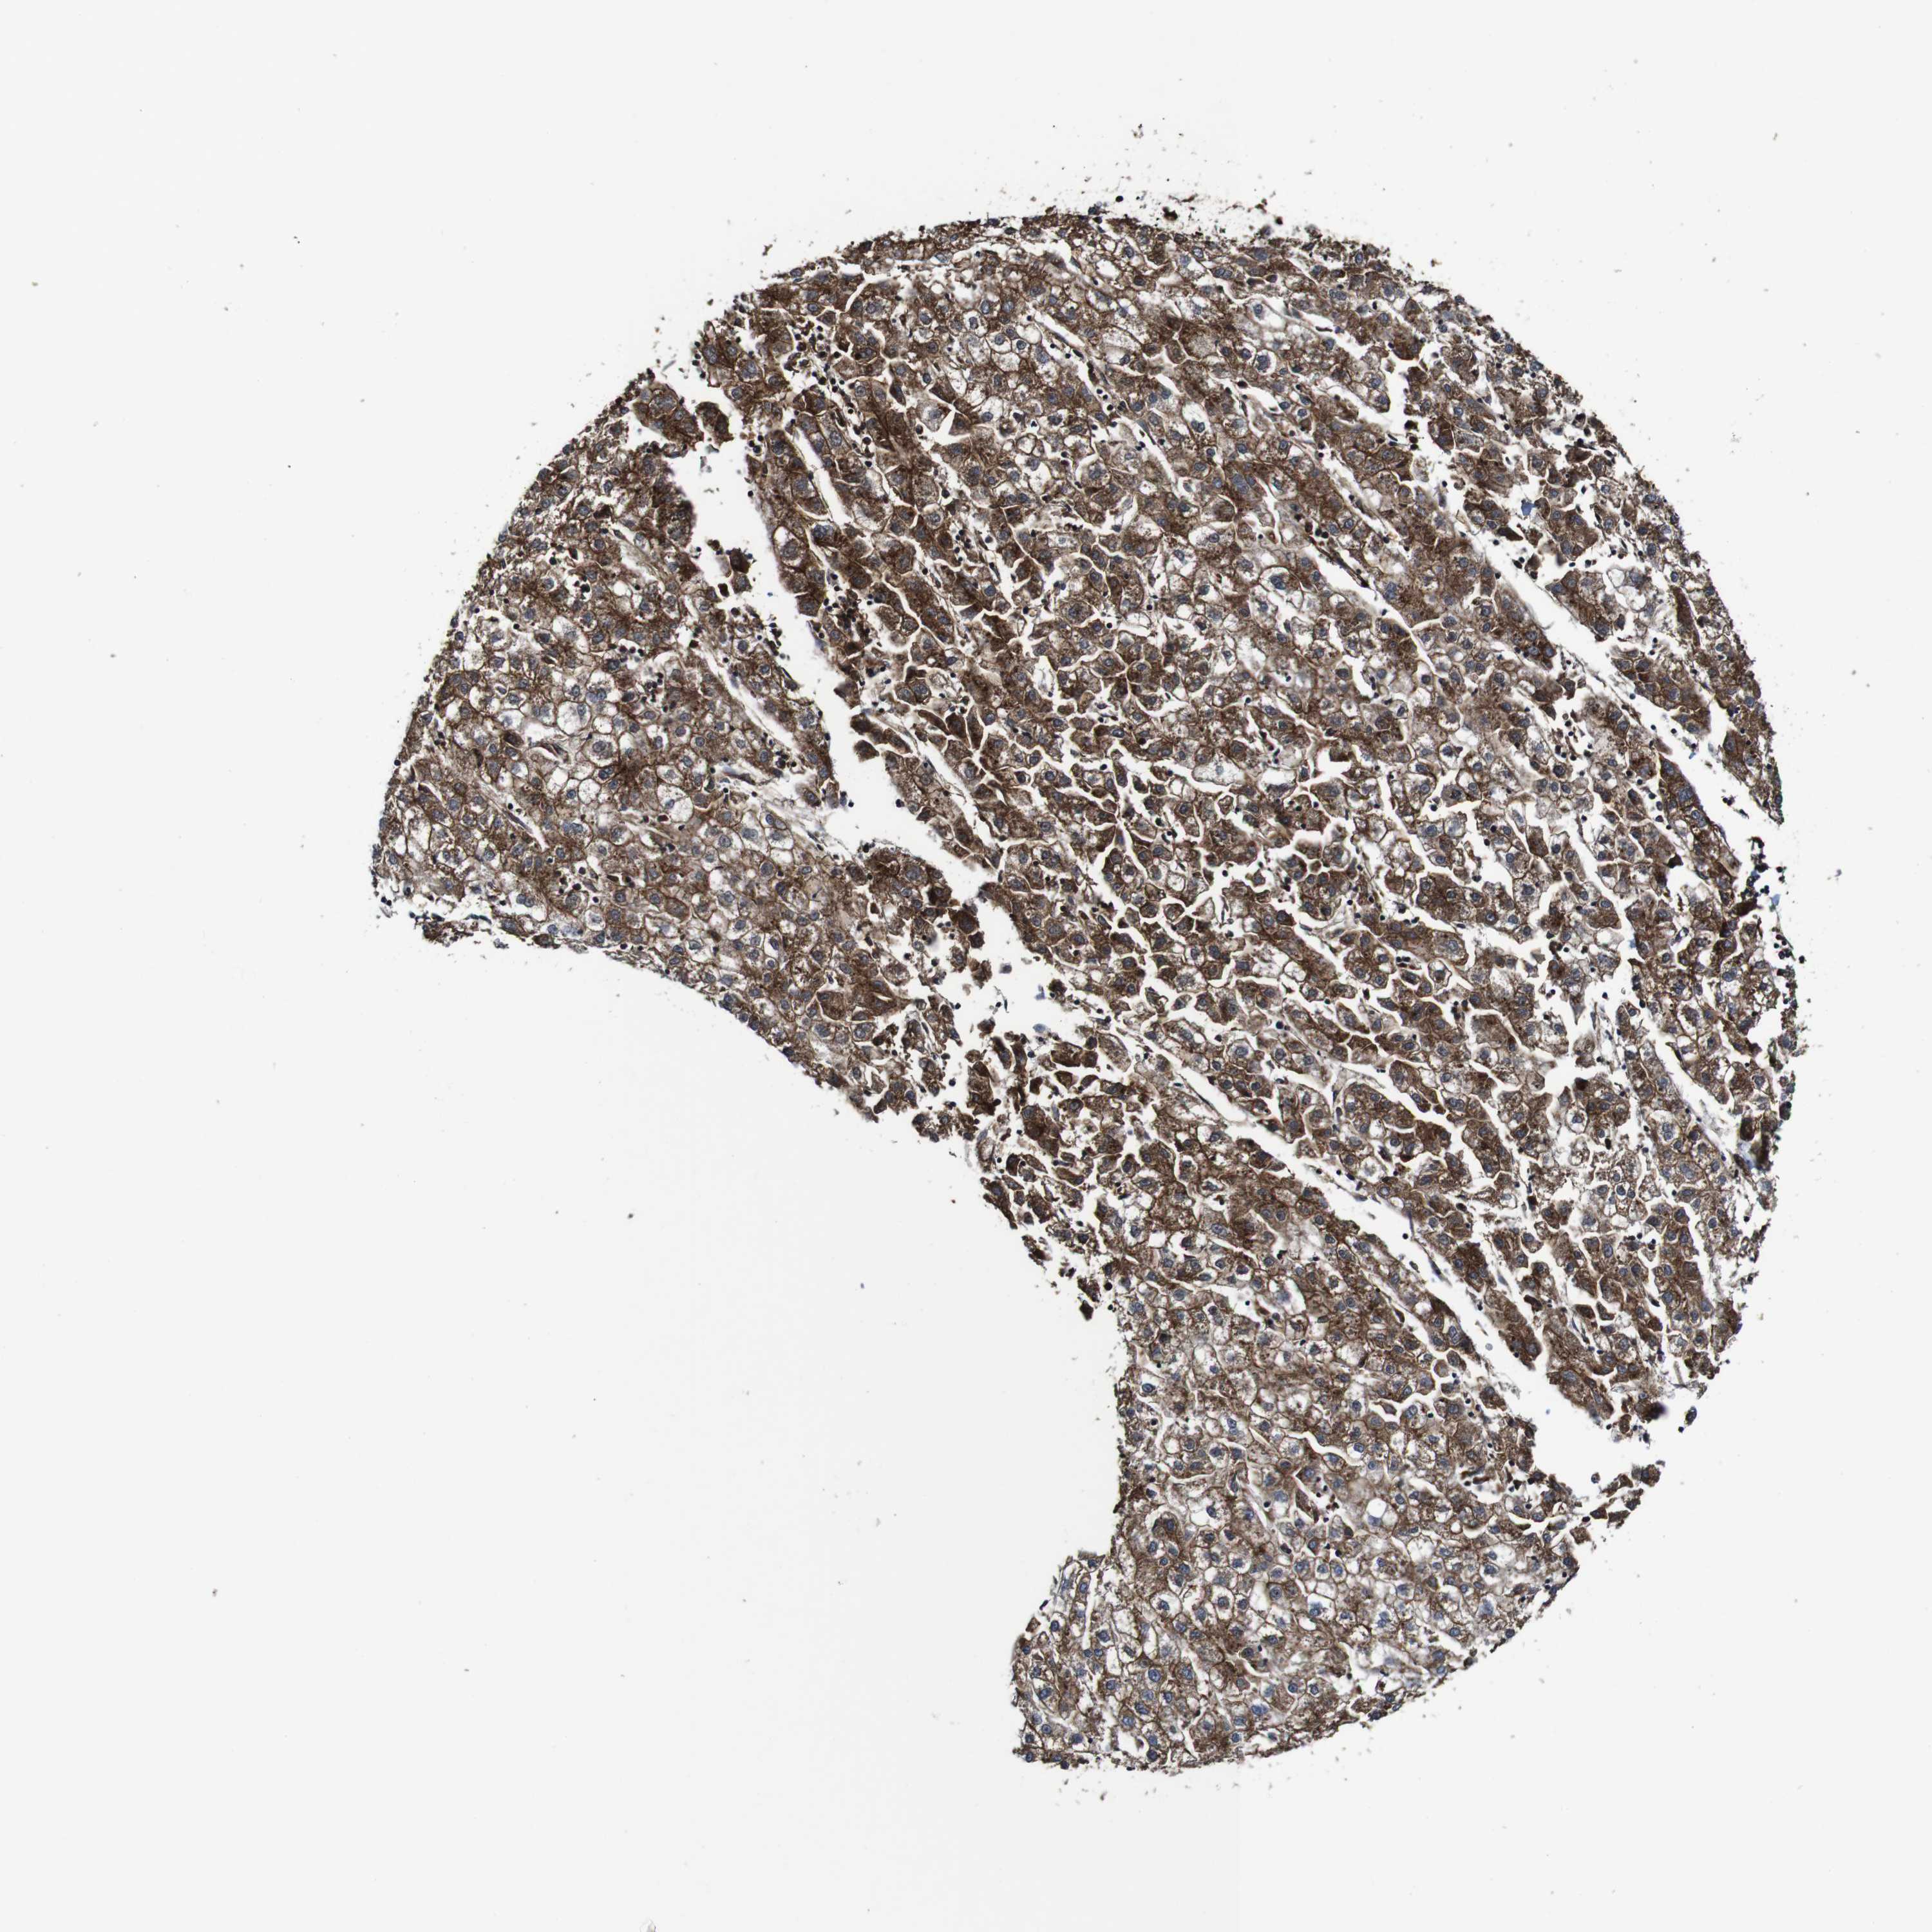

LIVER CANCER - Protein expressioni

A mouse-over function shows sample information and annotation data. Click on an image to view it in a full screen mode. Samples can be filtered based on level of antibody staining by selecting one or several of the following categories: high, medium, low and not detected. The assay and annotation is described here.

Note that samples used for immunohistochemistry by the Human Protein Atlas do not correspond to samples in the TCGA dataset.

Antibody stainingi

Antibody staining in the annotated cell types in the current human tissue is reported as not detected, low, medium, or high, based on conventional immunohistochemistry profiling in selected tissues. This score is based on the combination of the staining intensity and fraction of stained cells.

Each image is clickable and will lead to virtual microscopy that enables deeper exploration of all samples and also displays staining intensity scores, fraction scores and subcellular localization as well as patient and tissue information for each sample.

Antibody HPA012128

Antibody HPA012297

Staining

High

Medium

Low

Not detected

Intensity

Strong

Moderate

Weak

Negative

Quantity

>75%

75%-25%

<25%

None

Location

Nuclear

Cytoplasmic/membranous

Cytoplasmic/membranous,nuclear

Cholangiocarcinoma

Carcinoma, Hepatocellular, NOS